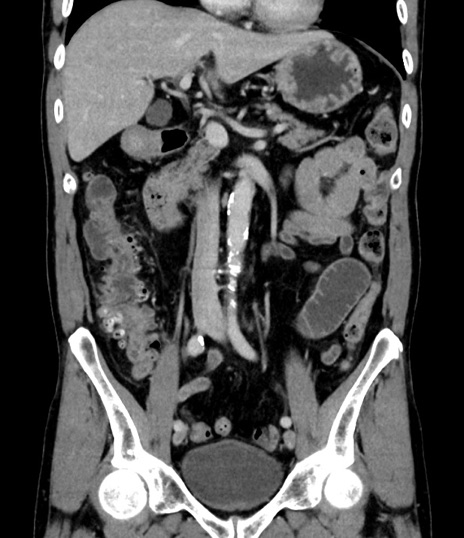

横断像

【症例】 60歳代男性

【主訴】 黒色吐物

【現病歴】 4日前から嘔気自覚、2日前の朝食後にも嘔気あり、自分で手で嘔吐反射起こし嘔吐したところ血が混ざっていたため受診。

【既往歴】 5年前汎発性腹膜炎を伴う急性虫垂炎で手術、高血圧、前立腺肥大症、高脂血症

【身体所見】 腹部正中に手術癩痕あり 腹部平坦・軟圧痛なし膨満感あり

【データ】WBC 8400、CRP 4.54